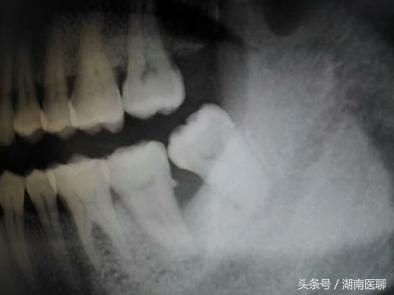

医生:固然你的智齿不痛不痒,但是位置不正,先上两张曲不雅图看看邓旋。

(智齿位置不正)

那别离是右下和左下两颗智齿邓旋,就是因为位置不正,固然它本身没坏,但它把前面的牙齿毁坏出一个大洞,也就是“虫牙”,然后拖着没处置,招致牙髓也传染了,牙髓炎爆发痛得他人不要不要的,你也想尝尝吗?